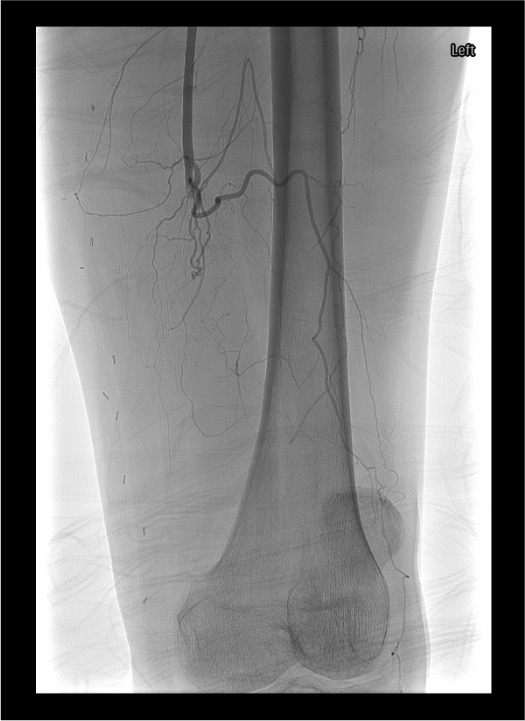

Angiographic Assessment & Endpoints

- Runoff angiography through sheath: 4 mL/s × 8 mL for outflow vessels; increase to 16–20 mL for lower leg and foot imaging

- Document baseline outflow to foot before initiating any intervention

- After crossing occlusion, gentle test injection to confirm intraluminal position and distal flow

- Select infusion catheter (Unifuse) to span entire lesion length; available in 10 cm increments (10–50 cm)

- Angiographic endpoints: restoration of inline flow, resolution of filling defects, treatment of underlying lesion

- If >50 cm occlusion, position 50 cm catheter with proximal marker at proximal extent; lytic medication flows distally as flow re-establishes